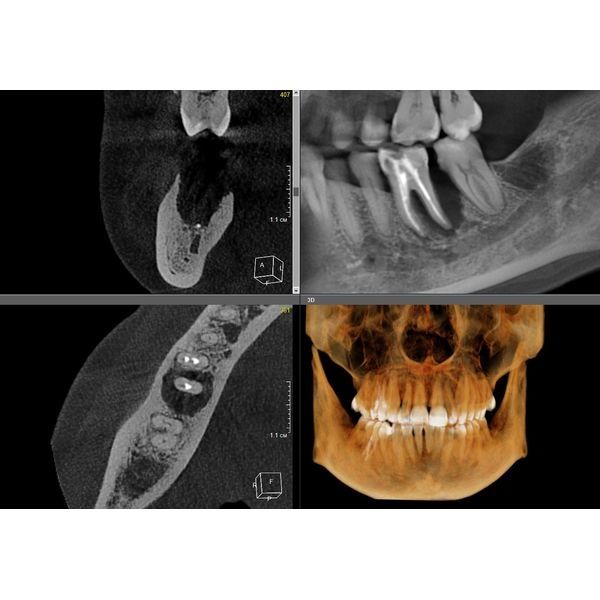

Провели компьютерную томографию — КЛКТ, т. е. 3D-рентген обеих челюстей: выявили неравномерную деструкцию костной ткани в области жевательной группы зубов нижней челюсти до 2/3 длины корня зуба, в области остальных зубов — до 1/3 длины корня.

После профессиональной гигиены и закрытого кюретажа было достигнуто купирование воспалительного процесса: уменьшились отёк, кровоточивость и глубина пародонтальных карманов. Пациентка была обучена подобранной системе гигиены, что позволило закрепить результат и перевести заболевание в стадию ремиссии.

Ключевым этапом стало ортодонтическое лечение. Оно позволило нормализовать окклюзионные контакты и перераспределить жевательную нагрузку, устранив основной фактор перегрузки в области поражённых моляров.